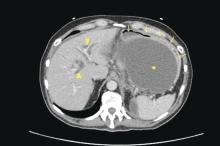

Walled-off necrosis: Arrows indicate mature capsule with heterogenous densities within the collection.

Patients with AP frequently develop peripancreatic fluid collections (PFCs). Based on the revised Atlanta classification, those are categorized into four types (Table 2, Figures 1-4).

The majority of acute PFCs in patients without evidence of pancreatic necrosis regress within a few weeks and thus intervention is not indicated early in the disease course. Current literature supports delaying the drainage/debridement of such collections for several weeks. The mortality from interventions decreases as the time to intervention from onset of symptoms increases41. Delaying intervention gives more time for recovery from systemic complications and allows the encapsulating wall and contents to organize further.

It is only the mature PFCs, which are symptomatic resulting in abdominal pain, nausea, early satiety, gastric outlet obstruction, failure to thrive, and/or biliary obstruction, that need to be drained/debrided42. Minimally invasive approaches have shown to result in better outcomes when compared to open laparotomy. Minimally invasive approaches include placement of percutaneous drainage catheters by interventional radiology (retroperitoneal approach preferred when feasible), endoscopic drainage/debridement, laparoscopy, and retroperitoneal necrosectomy following a step-up approach43.